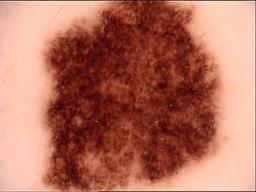

Skin lesion datasets provide essential information for understanding various skin conditions and developing effective diagnostic tools. They aid the artificial intelligence-based early detection of skin cancer, facilitate treatment planning, and contribute to medical education and research. Published large datasets have partially coverage the subclassifications of the skin lesions. This limitation highlights the need for more expansive and varied datasets to reduce false predictions and help improve the failure analysis for skin lesions. This study presents a diverse dataset comprising 12,345 dermatoscopic images with 40 subclasses of skin lesions, collected in Turkiye, which comprises different skin types in the transition zone between Europe and Asia. Each subgroup contains high-resolution images and expert annotations, providing a strong and reliable basis for future research. The detailed analysis of each subgroup provided in this study facilitates targeted research endeavors and enhances the depth of understanding regarding the skin lesions. This dataset distinguishes itself through a diverse structure with its 5 super classes, 15 main classes, 40 subclasses and 12,345 high-resolution dermatoscopic images.